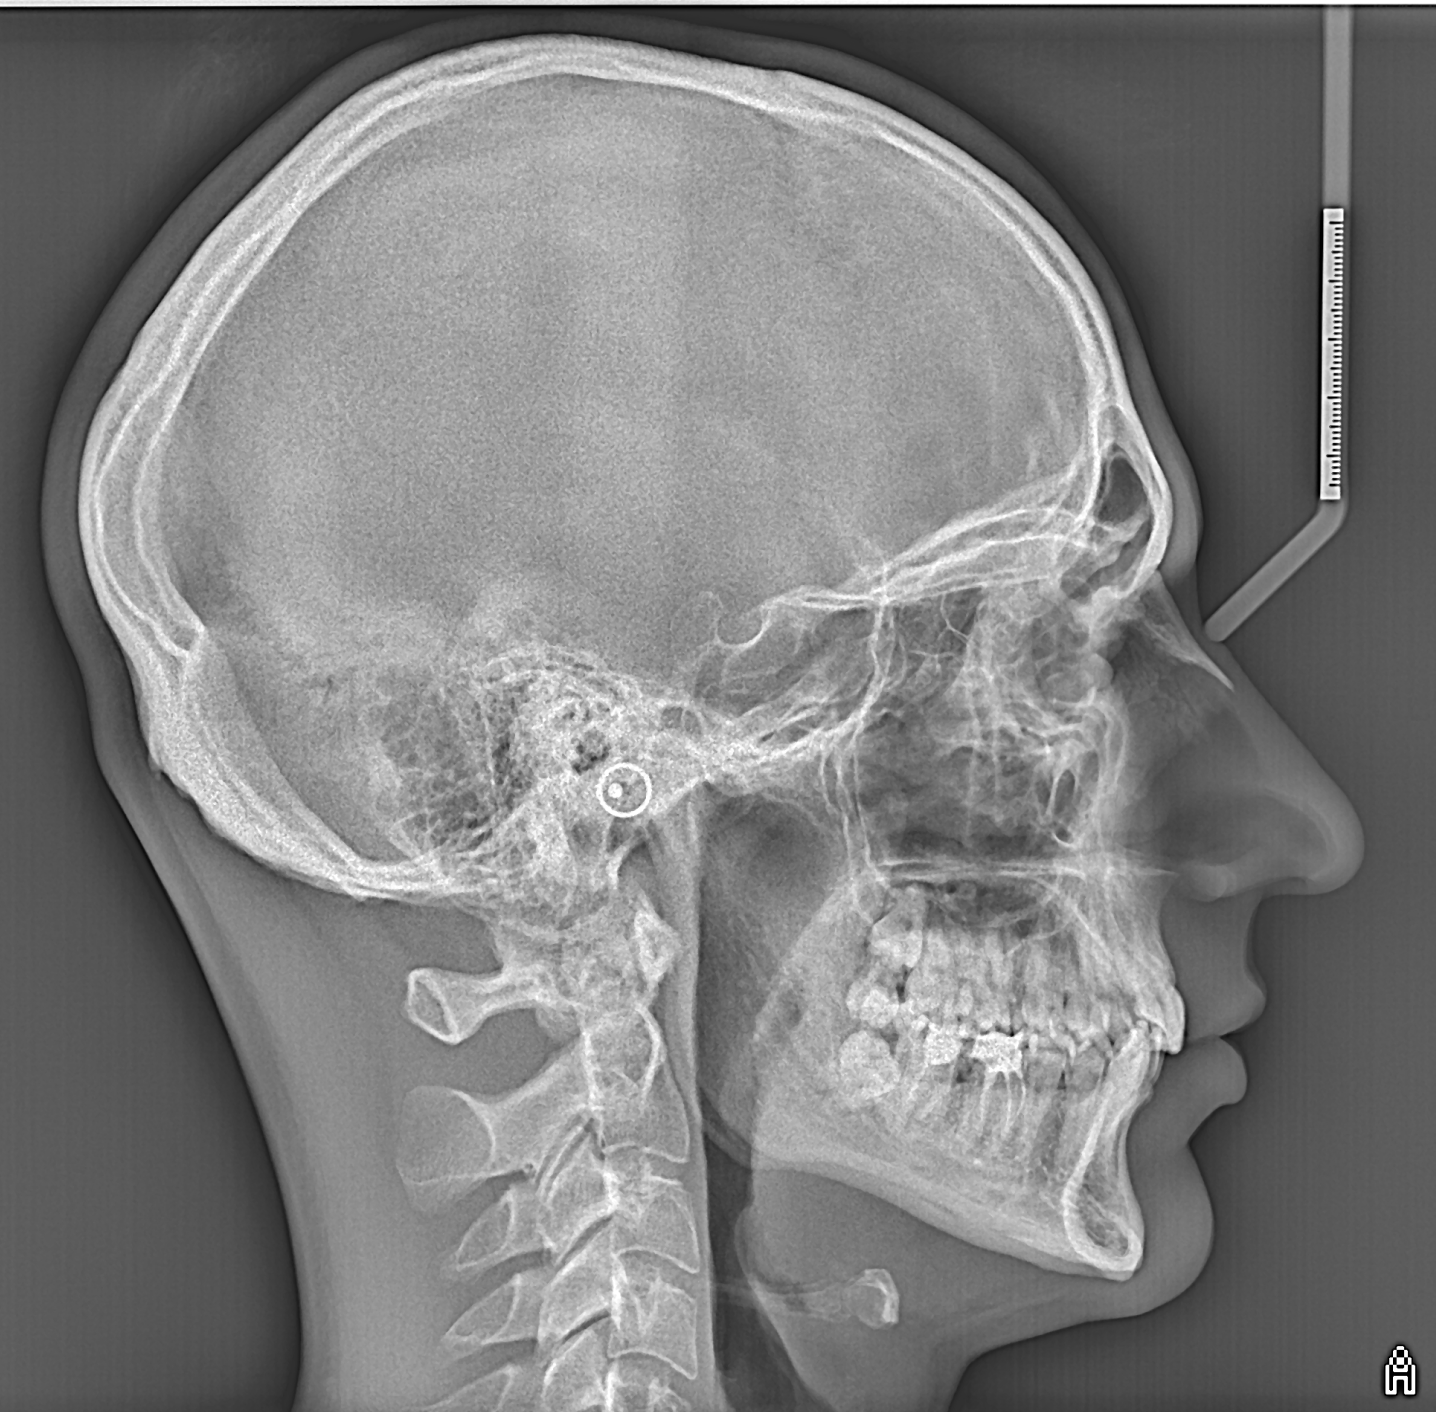

ТРГ бічної проекції

Телерентгенографія - це плоске двовимірне обстеження черепа в різних проекціях:

- Прямій

- Бічній

ТРГ є одним із найпопулярніших методів діагностики в ортодонтичній практиці, оскільки дозволяє оцінити скелетні співвідношення і провести необхідні вимірювання для корекції основних відхилень у структурі зубої̈щелепної системи: наприклад, розміру і положення щелеп, форми зубних дуг, розміру та прорізування зубів. Для більш точного аналізу в різних проекціях та виключення накладення тіней необхідна об'ємна комп'ютерна томографія, яка має максимальну інформативність.